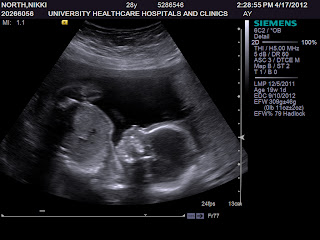

This was actually the first image, and still my favorite. Curled completely up like a potato bug ball.